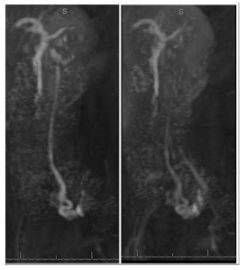

Pelvic ultrasound was unremarkable but Magnetic resonance angiography (MRA) pelvis revealed engorged bilateral paravaginal vessels and enlarged bilateral pelvic varices (Figure 1) (Figure 2). Post-contrast images with Valsalva demonstrated reflux into the left gonadal vein with left pelvic varices. The left pelvic varix measured 0.9cm and the right pelvic varix measured 0.7cm. The left gonadal vein measured 0.5cm in the short axis. There was antegrade filling of the right paravaginal vessels with Valsalva. These findings were compatible with PCS with reflux into the left gonadal vein.

Figure 2 Sagittal Posts MRA of Pelvis. Vessels: Engorged bilateral paravaginal vessels and enlarged bilateral pelvic varices noted. Post contrast images with Valsalva demonstrate reflux into the left gonadal vein with left pelvic varices. The left pelvic varix measures 0.9cm. A right pelvic varix measures 0.7cm. The left gonadal vein measures 0.5cm in short axis. There is antegrade filling of the right paravaginal vessels with Valsalva. The findings are compatible with pelvic congestion syndrome with reflux into the left gonadal vein.